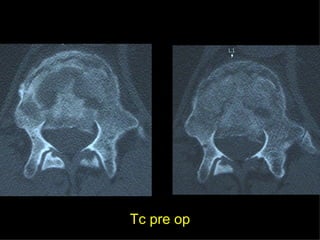

Tc pre op